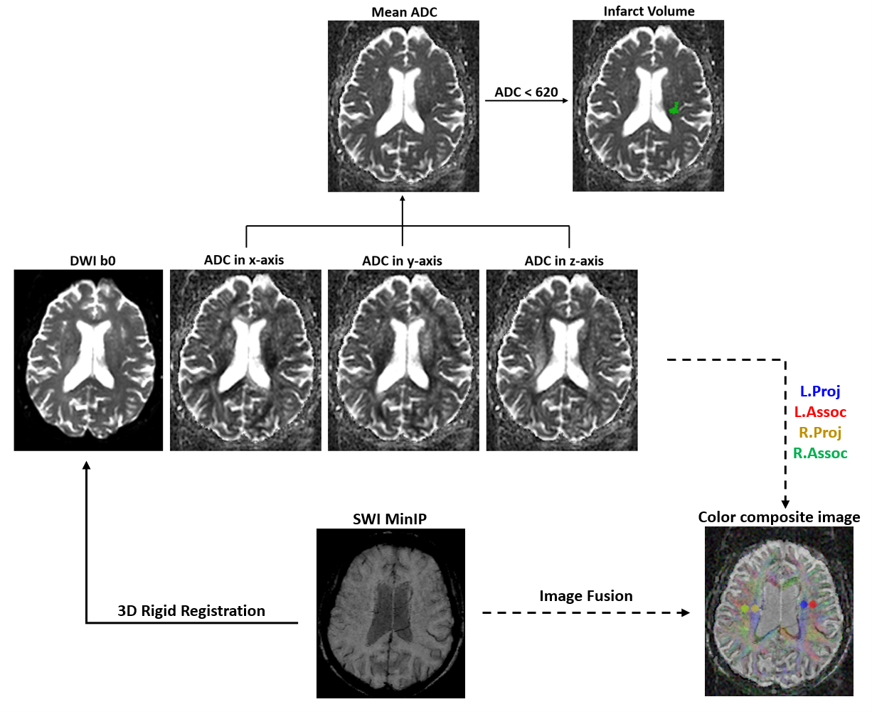

Apparent diffusion coefficient (ADC) images in the x-axis, y-axis and z-axis were calculated from the DWI b0 and b=1000 images of the x-, y- and z-axis. The mean ADC were defined by averaging ADCs in all three directions and were used to predict the infarct volume (ADC<620×10-6mm2/s). The SWI images were aligned to DWI space and fused with the ADC images in order to see medullary veins clearly. As shown in Figure 2, the four ROIs were manually defined on the fusion images. The DWI-ALPS index was calculated according to the equation in Figure 2. SPSS (version 26.0, IBM Corp, Armonk, NY, USA) was applied for the association between DWI-ALPS and PSCI. Statistical significance was defined as P < 0.05 (two‐sided).

Figure 2. Flowchart of DWI-ALPS index calculation. The Mean ADC was obtained by averaging the ADC images in the x, y, z directions. The SWI images were aligned to DWI space and fused with the ADC images in all three directions. The projection and association fiber ROIs were manually identified on the fusion images. DWI-ALPS index=mean (ADCxproj, ADCxassoc)/mean (ADCyproj, ADCzassoc).